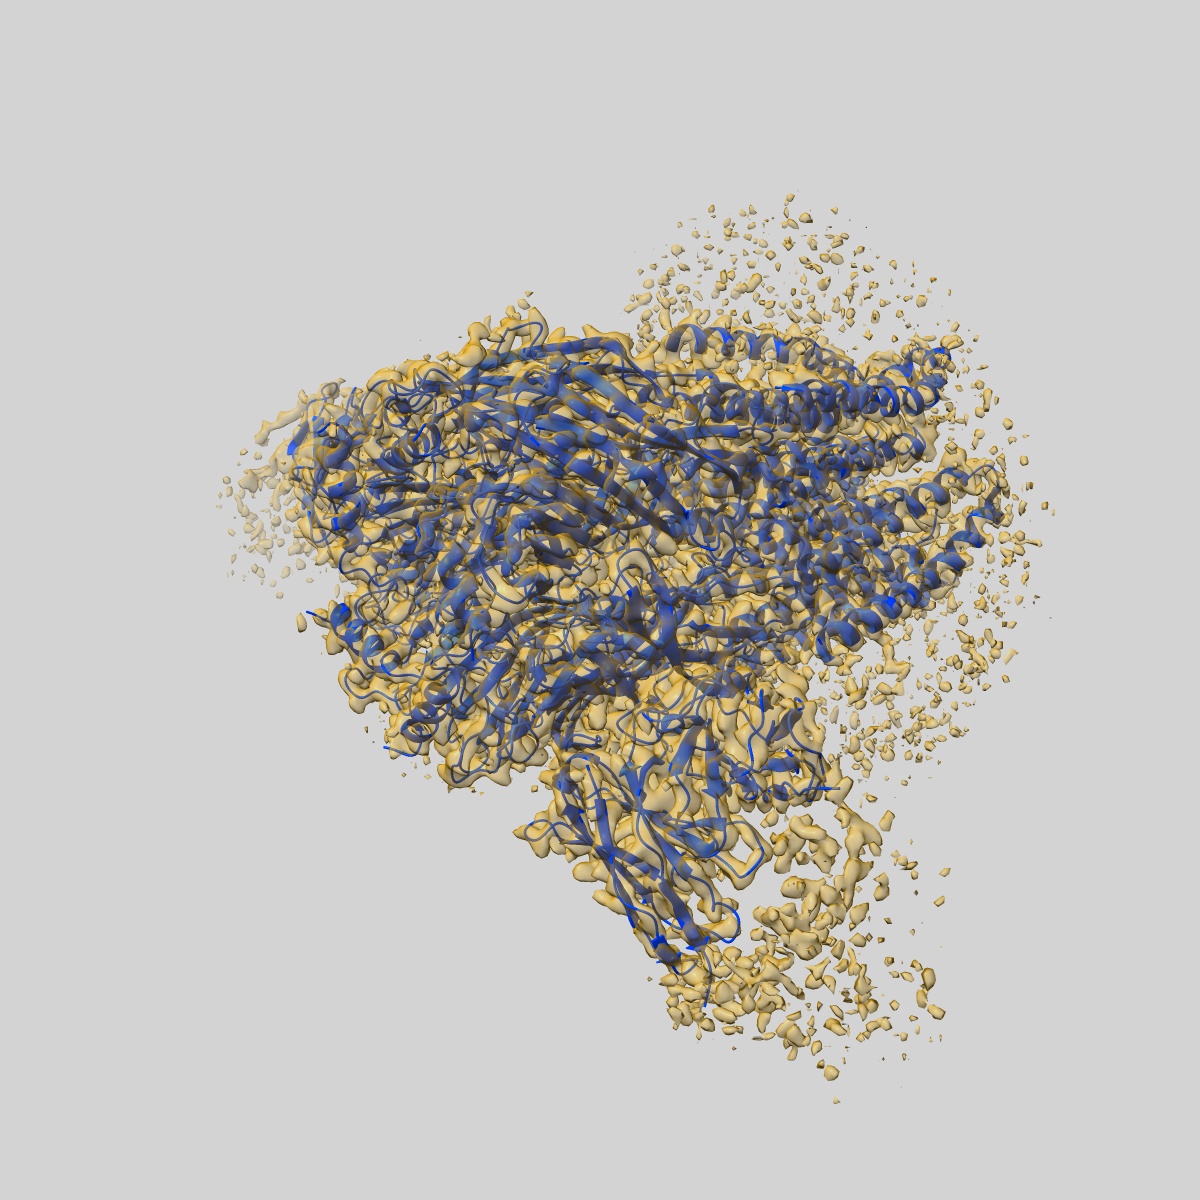

Human GABAA receptor alpha1-beta2-gamma2 subtype in complex with GABA plus picrotoxin

Sample: Human GABA-A receptor alpha1-beta2-gamma2 subtype in complex with GABA and picrotoxin

Fitted models: 6x40

Shared structural mechanisms of general anaesthetics and benzodiazepines.

Kim JJ, Gharpure A , Teng J, Zhuang Y , Howard RJ , Zhu S, Noviello CM, Walsh Jr RM , Lindahl E, Hibbs RE

(2020) Nature , 585 , 303 - 308